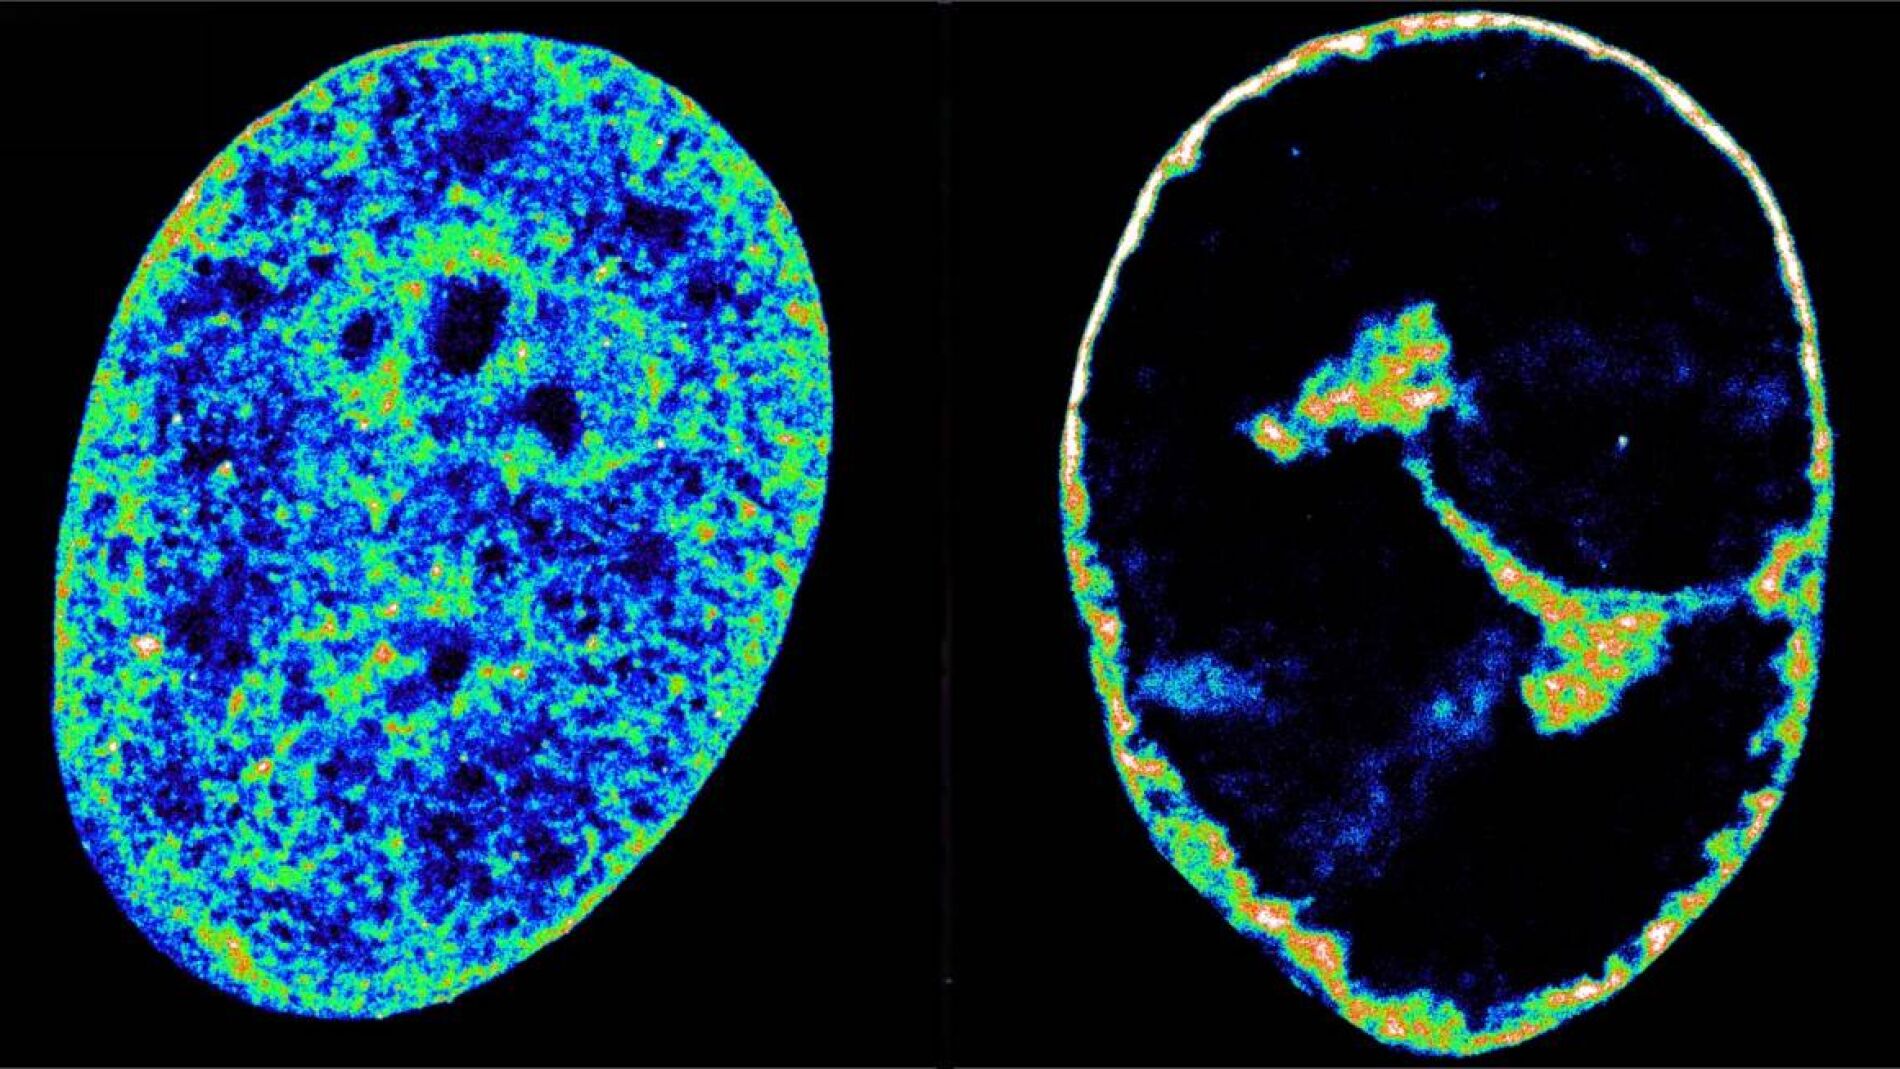

Los hallazgos fueron posibles combinando microscopía de superresolución, una técnica de imagen que puede ver estructuras de 20 nanómetros de ancho (algo aproximadamente 3.500 veces más fino que un cabello), con Hi-C, una técnica que revela qué fragmentos de ADN se están tocando dentro del núcleo. Utilizaron ambas técnicas para entender los mecanismos que usa VHS-1 para secuestrar a las células humanas.

El hurto molecular hace que la transcripción se venga abajo en todo el genoma del huésped, lo que a su vez provoca que la cromatina, el estado natural del genoma humano dentro de las células, se compacte en una cáscara densa de solo el 30% de su volumen original.

Este fue un hallazgo inesperado, ya que se creía que la estructura de la cromatina dicta la transcripción. "Siempre pensamos que la cromatina densa apagaba los genes, pero aquí vemos lo contrario: primero se detiene bastante la transcripción y luego el ADN se compacta. La relación entre actividad y estructura podría ser una calle de doble sentido", dice Álvaro Castells García, primer coautor del estudio e investigador del CRG.